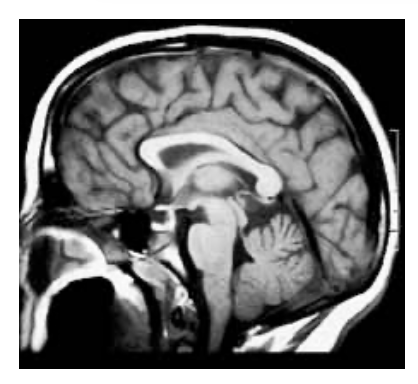

sagittal

corpus callosum